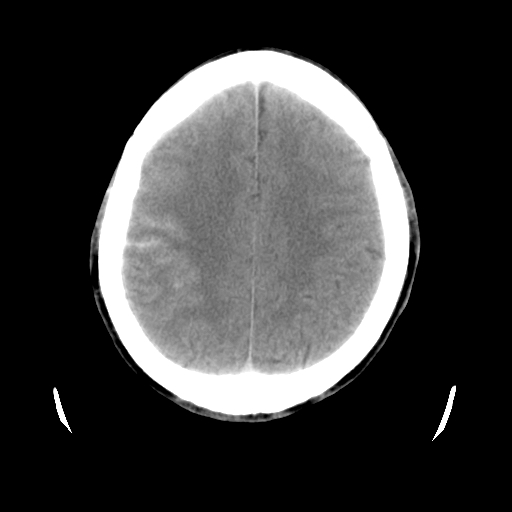

男,51岁,头外伤一小时,呕吐两次。

1)左侧中颅窝蝶骨翼后方硬膜外血肿。2)左侧颞顶部硬膜下血肿。3)蛛网膜下腔出血。4)左侧筛窦及双侧蝶窦炎症(或积血)。5)左侧额部头皮软组织肿胀。